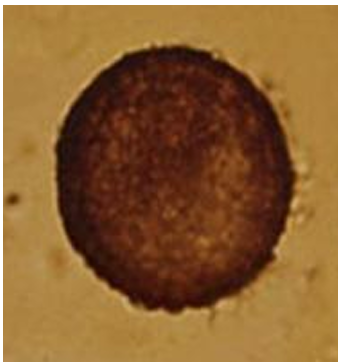

Toxascaris leonina